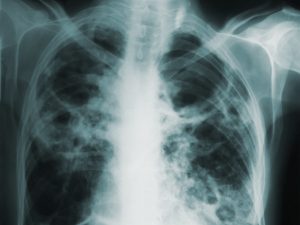

Central to this innovative approach is Siemens Healthineers' partnership with Qure.ai, a trailblazing Indian deep-learning tech company specializing in TB X-ray software. The cloud- or on-premises software from Qure.ai, which has two FDA certifications for heart failure and lung X-ray platforms, has shown that it can quickly and cheaply find TB cases.

Notably, the implications of this development are far-reaching. By augmenting routine chest X-ray interpretation with AI capabilities, diagnoses can be rendered swiftly and accurately. This not only expedites treatment for affected individuals but also curtails the transmission of TB. It is estimated that one untreated TB patient has the potential to infect up to 15 people annually, underscoring the urgency of early detection.